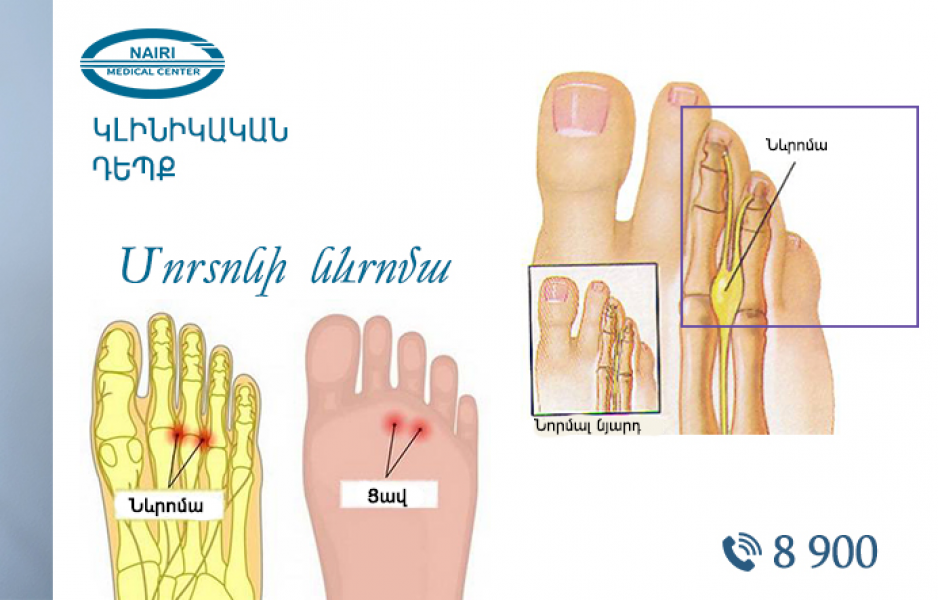

Կլինիկական դեպք. Մորտոնի նևրոմայի վիրահատական բուժում

«Նաիրի» բժշկական կենտրոն է ընդունվել 60 տարեկան պացիենտ, որը գանգատվում էր ոտնաթաթի ուժեղ ցավից: Ցավը ոտքի երրորդ-չորրորդ մատների ներբանային մակերեսից ճառագայթում էր դեպի ոտնաթաթի ծայրը...

21 Հոկտեմբեր 2022 | Էսթետիկ և պլաստիկ վիրաբուժություն